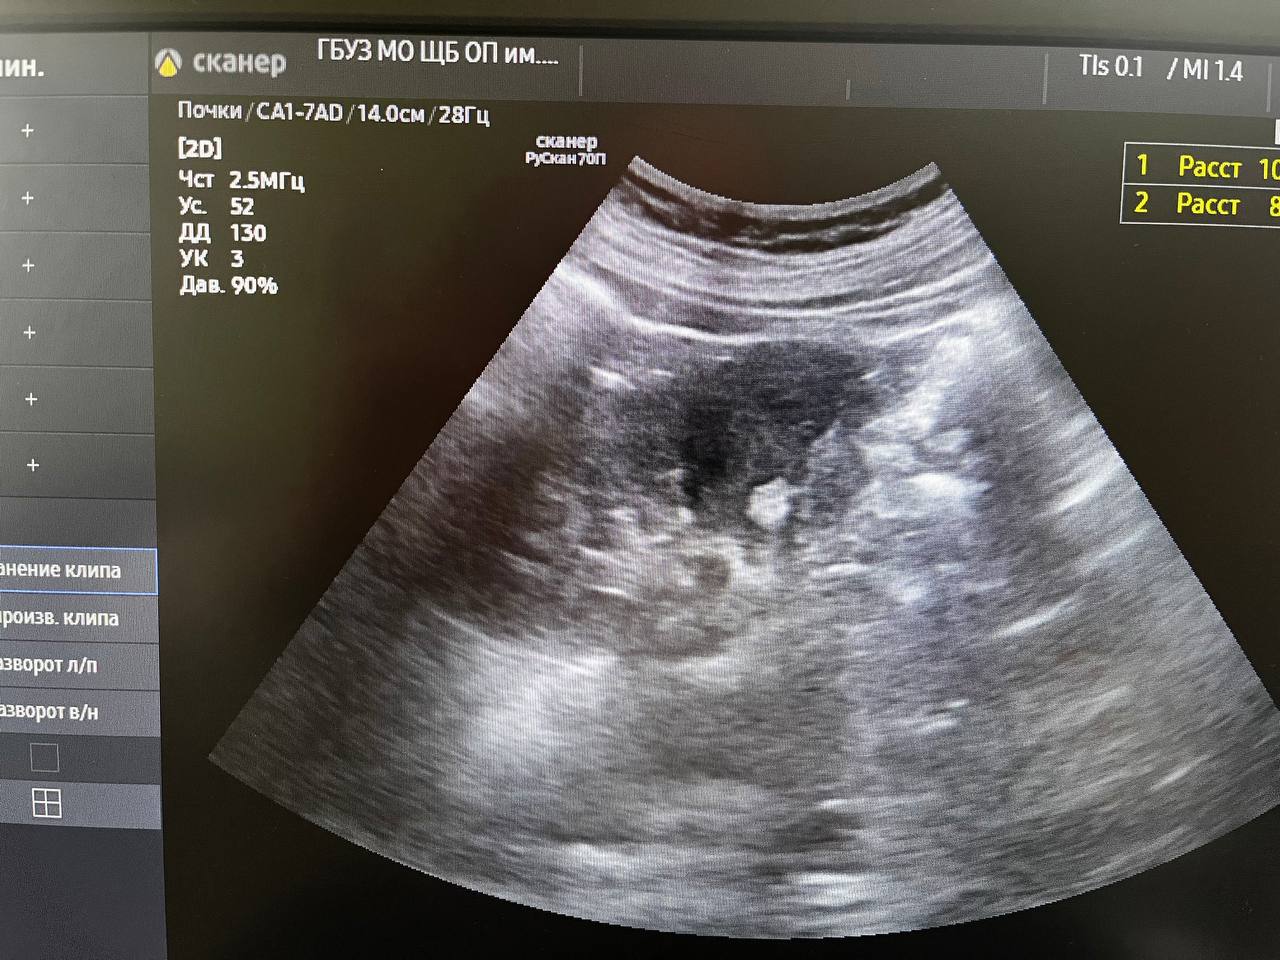

В минувшую субботу в день здоровой почки проверить своё здоровье пришли 22 человека. У двоих из них выявлены серьёзные патологии при полном отсутствии жалоб. Остальные пациенты были с мелкими кистами почек до 10мм и "песочком". Всем выполнено УЗИ, выданы направления на лабораторные обследования. Так же были пациенты без патологии, пришедшие для комплексного обследования со стороны мочевыделительной системы, выполнено УЗИ, выданы направления на общий анализ мочи

"У одного пациента - мочекаменная болезнь, чашечные камни с обеих сторон до 15мм. Направлен на МСКТ для установления точной локализации и положения камней с целью подготовки для плановой госпитализации и оперативного лечения. У второго пациента выявлено образование в правой почке до 12мм. Пациент направлен на МСКТ для верификации",

- уточнил врач-уролог поликлиники для взрослых обособленного подразделения им. М.В. Гольца Щёлковской больницы в г. Фрязино Владимир Орленко